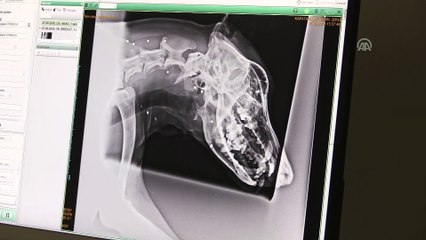

Kastamonu’nun Cide ilçesinde kimliği belirsiz kişiler tarafından tüfekle vurulan ve ağır yaralanan iki köpek, tedavi altına alındı.